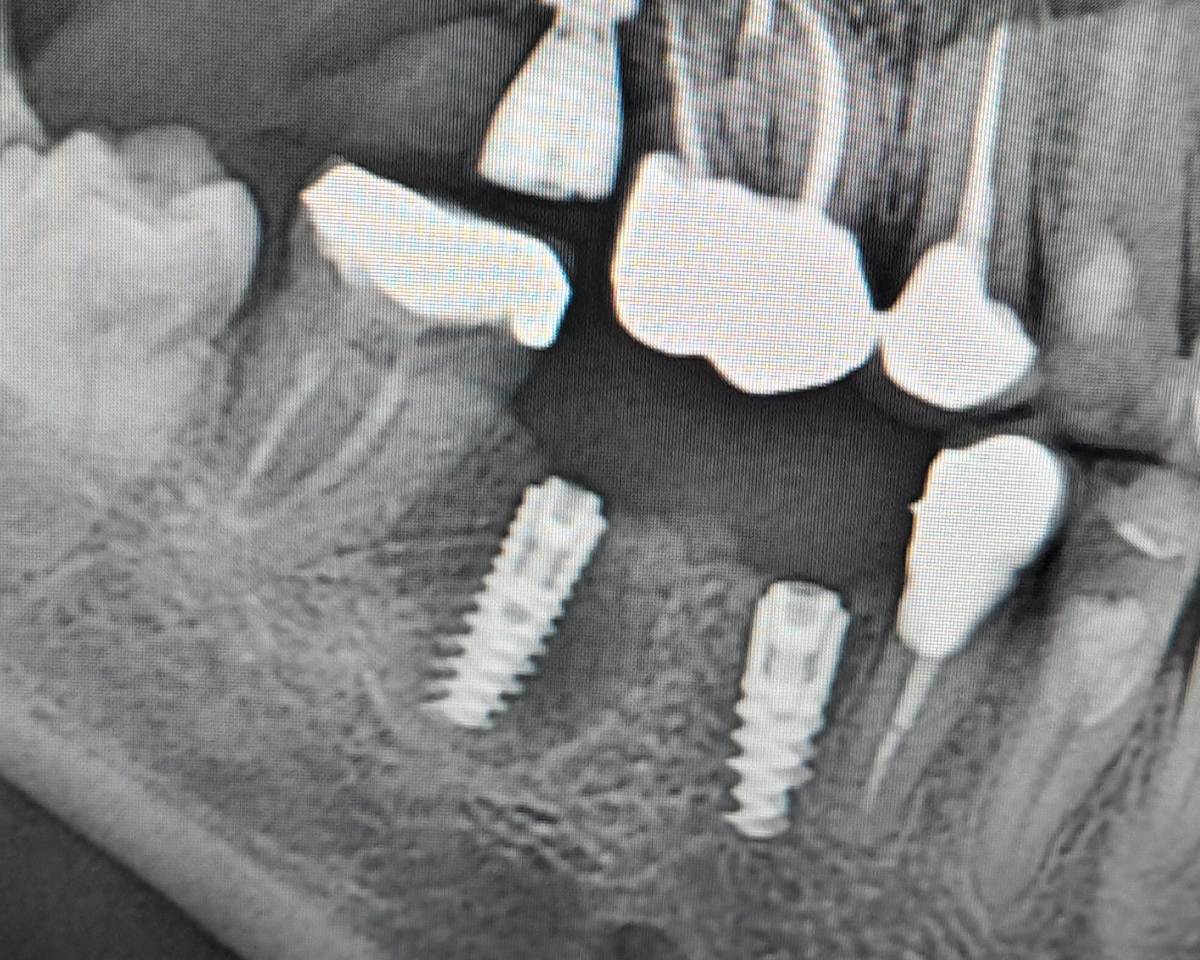

Irina xyz Опубликовано 21 час назад Поделиться Опубликовано 21 час назад (изменено) Добрый день, 4й день после установки импланта 45 начал тянуть соседний зуб -клык на нижней челюсти (боль притупляется при давлении/нажатии на зуб) - это нормально? Изменено 21 час назад пользователем Irina xyz Приблженное фото, крупное изображение Ссылка на комментарий

Irina xyz Опубликовано 20 часов назад Автор Поделиться Опубликовано 20 часов назад Это более общий план Имплант на 45м - 3.5 мм диаметр, 10 - длина Ссылка на комментарий